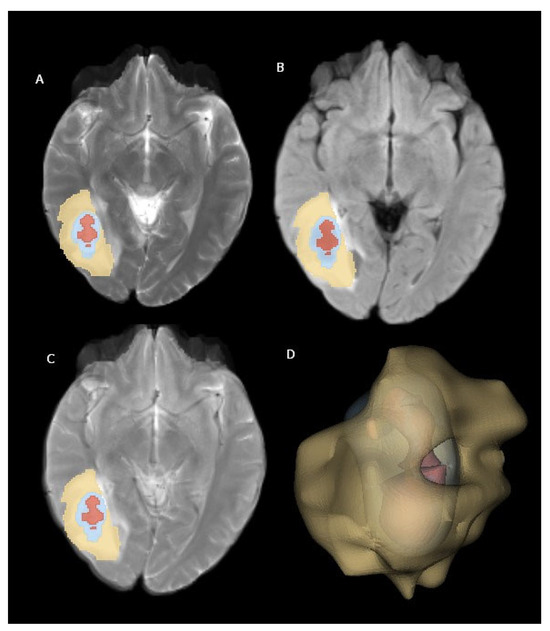

Using VTK, a three-dimensional model was constructed for each tumor region. These individual tumor models were then merged to create a composite representation. Finally, the generated 3D models were superimposed onto the corresponding MR images and visualized using Matplotlib (https://matplotlib.org/) and Seaborn (https://seaborn.pydata.org/). Figure 2 illustrates examples of brain metastasis in a patient diagnosed with non-small-cell lung cancer, rendered using the abovementioned 3D visualization technique.

The feature extraction process encompassed five filter types (original, Laplacian of Gaussian, logarithm, exponential, and wavelet) and three feature classes (first-order, texture, and shape) applied to the perilesional edema area (Figure 2). The filters and feature classes selected to characterize the peritumoral edema region enable a detailed and accurate analysis of the area. The original filter serves as a reference by reflecting the basic features of the data. The Laplacian of Gaussian (LoG) filter enhances the edges and details in the image, making the boundaries of the perilesional edema more distinct. The logarithmic filter improves low-contrast regions and highlights small but important features, making it useful for capturing subtle changes in peritumoral edema. The exponential filter emphasizes rapidly changing features and brings out the irregular structures in the perilesional edema more clearly. The wavelet filter allows for an analysis of the image at different resolution levels, making it possible to examine multi-scale structures. As for feature classes, first-order features include basic statistical properties (e.g., intensity and contrast), texture features analyze the textural patterns and structure in the image, and shape features describe the geometric structures within the region. These filters and feature classes allow for the accurate and effective characterization of the peritumoral edema region, aiding the model in producing more precise and reliable results. This resulted in a total of 1130 features being extracted for each patient.

Figure 2. Brain metastasis from NSCLC located in right cerebral hemisphere. (A) T2-weighted images, (B) FLAIR-weighted images, (C) T2-FLAIR digital subtraction images, and (D) three-dimensional volume rendering of mass. Yellow: perilesional edema area; blue: contrast-enhanced area; red: necrosis area.